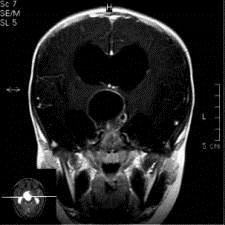

问题 病历摘要:??患者女性,6岁,半年来感觉视力模糊,近10天出现反复头痛,间有恶心呕吐,精神转差,查体:神志清楚,身高90cm,体重25Kg,血压90/55mmHg,右眼视力4.6,左眼视力4.8,双侧视乳头水肿,颈软,伸舌居中,四肢肌张力正常,肌力5级,双侧Babinski征(-)。 患者入院第三天,安排手术治疗,请选择最适用的手术入路。

选项 A.额下入路 B.翼点入路 C.终板入路 D.经胼胝体入路 E.经蝶窦入路 F.翼点-经胼胝体联合入路 G.额下-翼点联合入路 H.经脑室入路

答案 BF